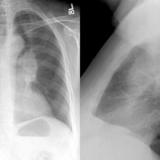

LUL Collapse Case 1 PA and Lateral

Date: 02/19/2004

Views: 3555